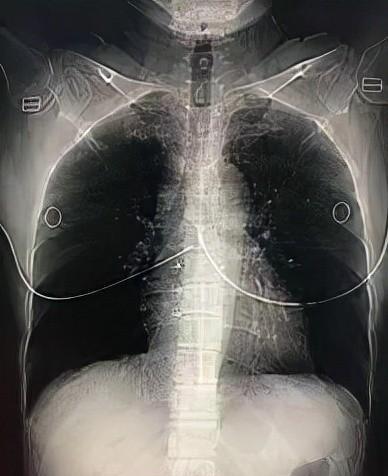

照胸部X光需要注意什么?

(1)照胸片前可以吃东西,但是由于X光的透光性,身体上不能穿戴任何有干扰的饰品。

比如内衣(主要是钢丝支架)、项链等金属物等,还要提前换上检查服,最好穿较薄的纯色衣服。

这里有一个误区,不是说不是金属就不碍事,牛仔服、衣服上的金丝线、油漆图案、膏药等都会影响诊断效果。

(2)照X光时,要采用站姿,前胸贴近底片,手插腰,还要听从医师的指示进行深呼吸并摒住呼吸。